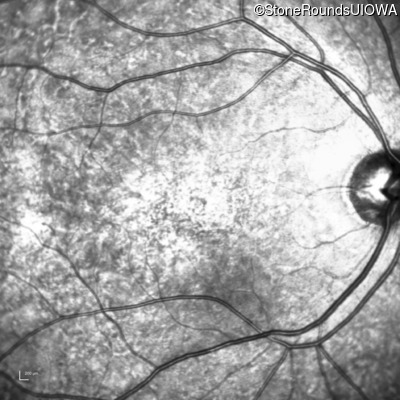

The clinical features favoring the diagnosis of ABCA4-associated autosomal recessive Stargardt disease in this patient include: loss of acuity at the beginning of the second decade, parafoveal photoreceptor loss on OCT, pisciform flecks in the macula with clear peripapillary sparing, and normally sighted parents.

All three of the cardinal ophthalmic features of Mendelian macular dystrophies are present in this patient. The most striking features of the fundus exam are the numerous yellow flecks at the level of the RPE. Flecks are most commonly seen in AR Stargardt disease and pattern dystrophy although they may be seen in some of the rarer Mendelian maculopathies as well. The visual acuity in patients with AR Stargardt disease is often "worse than the fundus looks" while the acuity in pattern dystrophy is often quite good despite extensive flecks. The pedigree of this patient is compatible with ABCA4-associated Stargardt disease and the better than expected acuity is attributable to foveal sparing (see below). The onset of reduced acuity at age 10 is much more characteristic of ABCA4 disease than pattern dystrophy. Another feature present in this patient that is very frequently seen in Stargardt disease is peripapillary sparing. However, this sign can be seen in pattern dystrophy as well. When central atrophy is present in ABCA4-associated Stargardt disease it often somewhat shiny (which is uncommon with the geographic atrophy of pattern dystrophy or age-related macular degeneration). Some patients with ABCA4-associated Stargardt disease can have some preservation of the fovea giving a zonal "bullseye" appearance to the center of the macula. Sometimes this preservation is associated with preserved acuity as in this case. The outer nuclear layer (ONL) is much thinner than normal on OCT, indicative of photoreceptor loss. This is associated with a thinning of the ellipsoid zone which is usually many times brighter and thicker than the external limiting membrane (ELM). These two lines are essentially equal in intensity in this patient. The foveal sparing is seen on OCT only as a small bit of retinal convexity in the center of the atrophy coupled with a small bit of residual RPE flanked by bare Bruch's membrane. The presence of a robust I2e isopter on Goldmann perimetry places this patient in the least severe half of all Stargardt patients (see Schindler, et al., 2010). Most patients with ABCA4-associated disease are somewhat myopic as is this patient. Stargardt patients also tend to perform very poorly on pseudoisochromatic plates, even when their acuity is still fairly good as it is here.